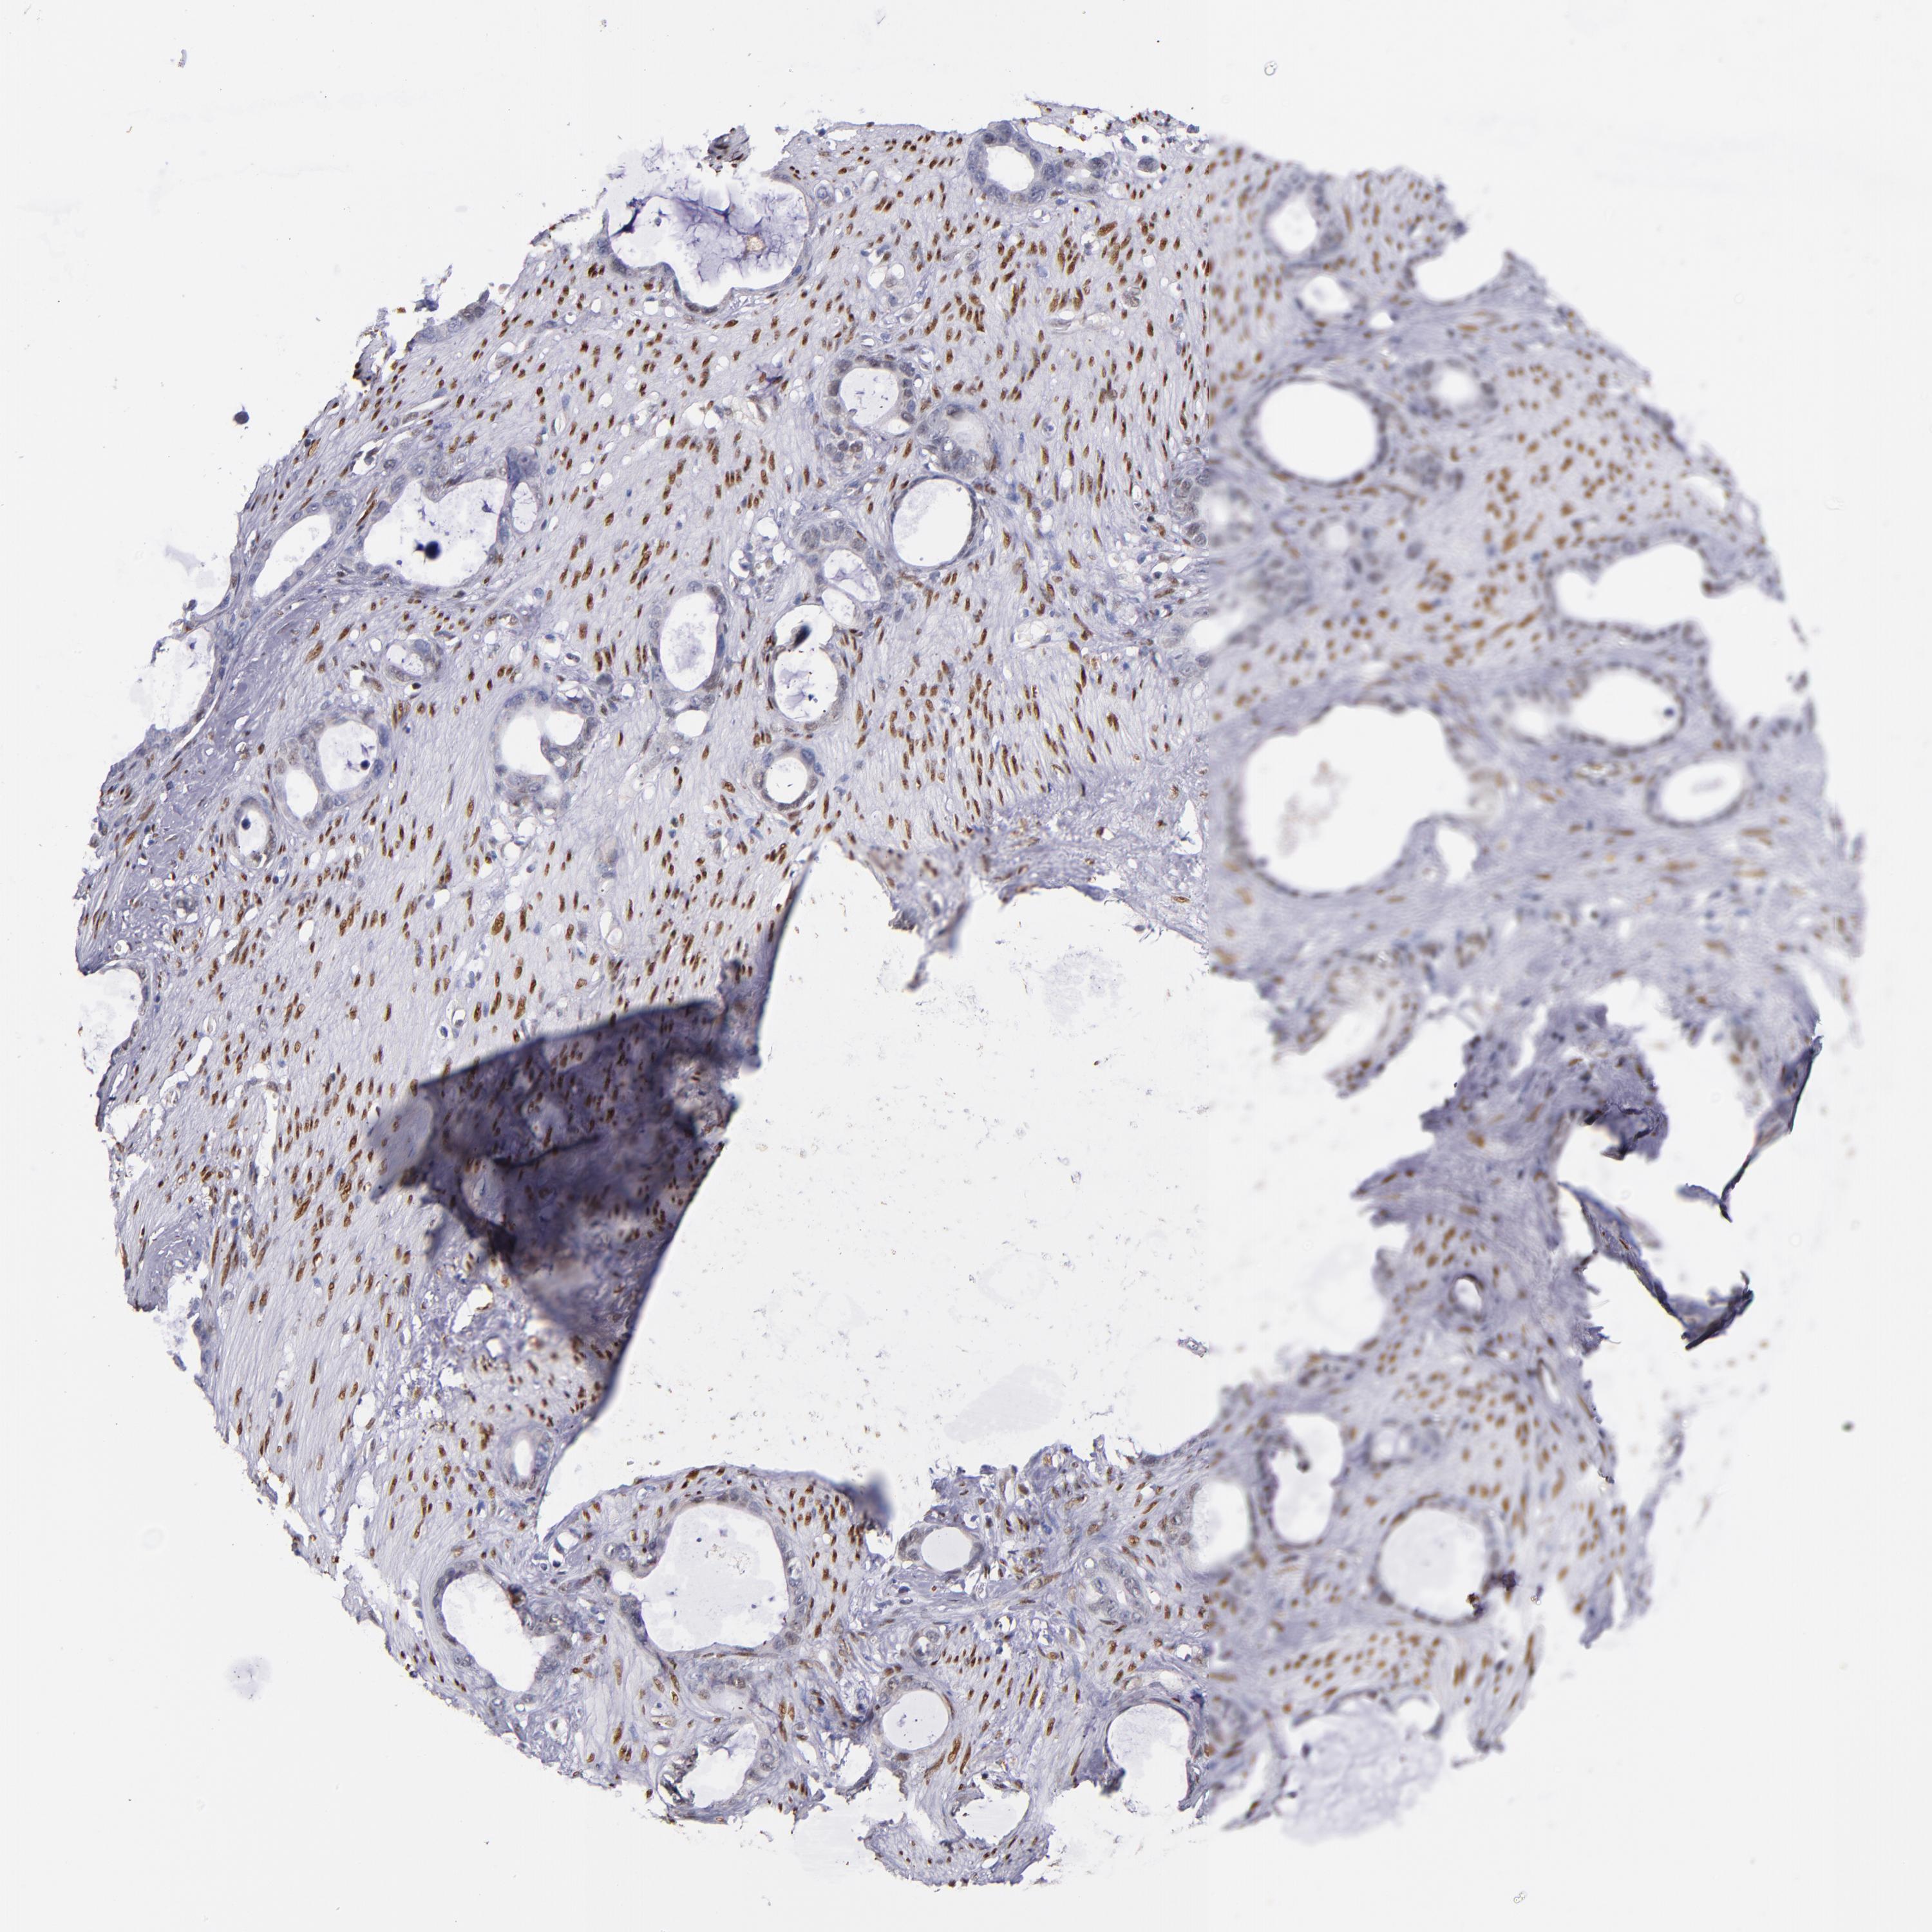

STOMACH CANCER - Protein expressioni

A mouse-over function shows sample information and annotation data. Click on an image to view it in a full screen mode. Samples can be filtered based on level of antibody staining by selecting one or several of the following categories: high, medium, low and not detected. The assay and annotation is described here.

Note that samples used for immunohistochemistry by the Human Protein Atlas do not correspond to samples in the TCGA dataset.

Antibody stainingi

Antibody staining in the annotated cell types in the current human tissue is reported as not detected, low, medium, or high, based on conventional immunohistochemistry profiling in selected tissues. This score is based on the combination of the staining intensity and fraction of stained cells.

Each image is clickable and will lead to virtual microscopy that enables deeper exploration of all samples and also displays staining intensity scores, fraction scores and subcellular localization as well as patient and tissue information for each sample.

Staining

High

Medium

Low

Not detected

Intensity

Strong

Moderate

Weak

Negative

Quantity

>75%

75%-25%

<25%

None

Location

Nuclear

Cytoplasmic/membranous

Cytoplasmic/membranous,nuclear

Adenocarcinoma, NOS

Adenocarcinoma, High grade